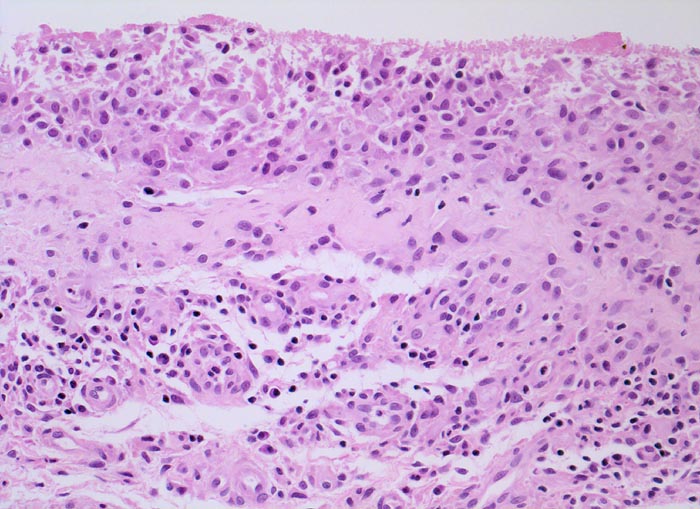

In Abhängigkeit von der Entzündungsdauer werden unterschiedliche morphologische Befunde beschrieben. Die initiale proliferative Phase ist charakterisiert durch eine Hyperplasie der Synovialis, Fibrinexsudate und Gelenkergüsse. In der destruktiven Phase kommt es zur Zerstörung von Gelenkknorpel und gelenknahem Knochen durch Ausbildung eines intraartikulären Pannusgewebes (> 194). Die ausgebrannte Phase ist gekennzeichnet durch eine synoviale Fibrose mit zunehmender Ankylose (= Gelenkversteifung).

Typische histologische Veränderungen sind eine synoviale Zottenhyperplasie, Verbreiterung der Deckzellschicht unter Einschluss mehrkerniger Riesenzellen, Fibrinexsudate und synoviale Ulzerationen, Infiltrate von Lymphozyten teils in Form von Lymphfollikeln, Plasmazellen, neutrophilen Granulozyten, Makrophagen und Siderophagen, sowie Einschlüsse von Knorpel- und Knochenfragmenten (Detritussynovialitis). Die histologischen Befunde der Synovialis korrelieren oft nicht mit den klinischen Angaben. Trotz fortgeschrittener Gelenkdestruktion mit ausgeprägter klinischer Symptomatik können Synovialektomiepräparate nur sehr geringe pathologische Veränderungen zeigen. Oft ist auch nicht mehr zu eruieren, welche Läsionen Folge der Grundkrankheit und welche Folge diverser intraartikulärer Therapien oder begleitender Superinfektionen sind.

• Synovialis mit verplumpten Zotten.

• Stark proliferierte mehrreihige synoviale Deckzellschicht.

• Herdförmig Fibrinauflagerungen durchsetzt von neutrophilen Granulozyten.

• Hyperzelluläres Stroma mit lymphoplasmazellulärem Entzündungsinfiltrat mit Ausbildung von Lymphfollikeln.